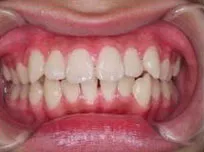

症例1

| 治療期間 | 11ヶ月(2021年6月〜2022年5月) |

| 費用 | 495,000円(税込) |

| リスクや副作用 | 成長期が終わった18歳以降に、2期矯正が必要になることがある |